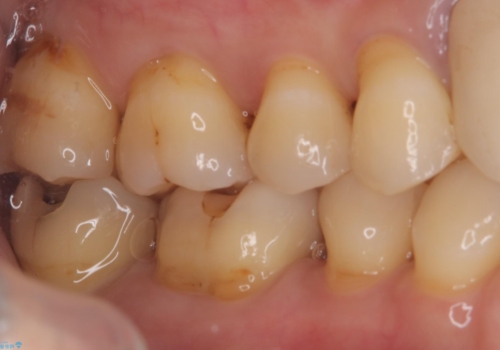

今回残存歯質量から破折のリスクを説明し、クラウンでのやり替えも提案しましたが歯質切削量が多くなることから一度インレーで様子を見ることとなりました。

セラミックインレーセット時はラバーダム防湿を行っています。